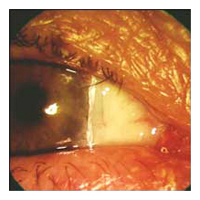

is a pinkish-yellow, triangular-shaped benign tissue growth starting from the nasal area of your eye and grows toward the cornea. As a pterygium grows, it can be varied in its appearance from small and pink to large and angry red with symptoms of dry eye. Eventually, it may cause visual disturbances by disrupting the normally smooth surface of the cornea. In severe cases, a pterygium can block a patient's vision altogether.

Before Pterygium Removal  After

Pterygium Removal